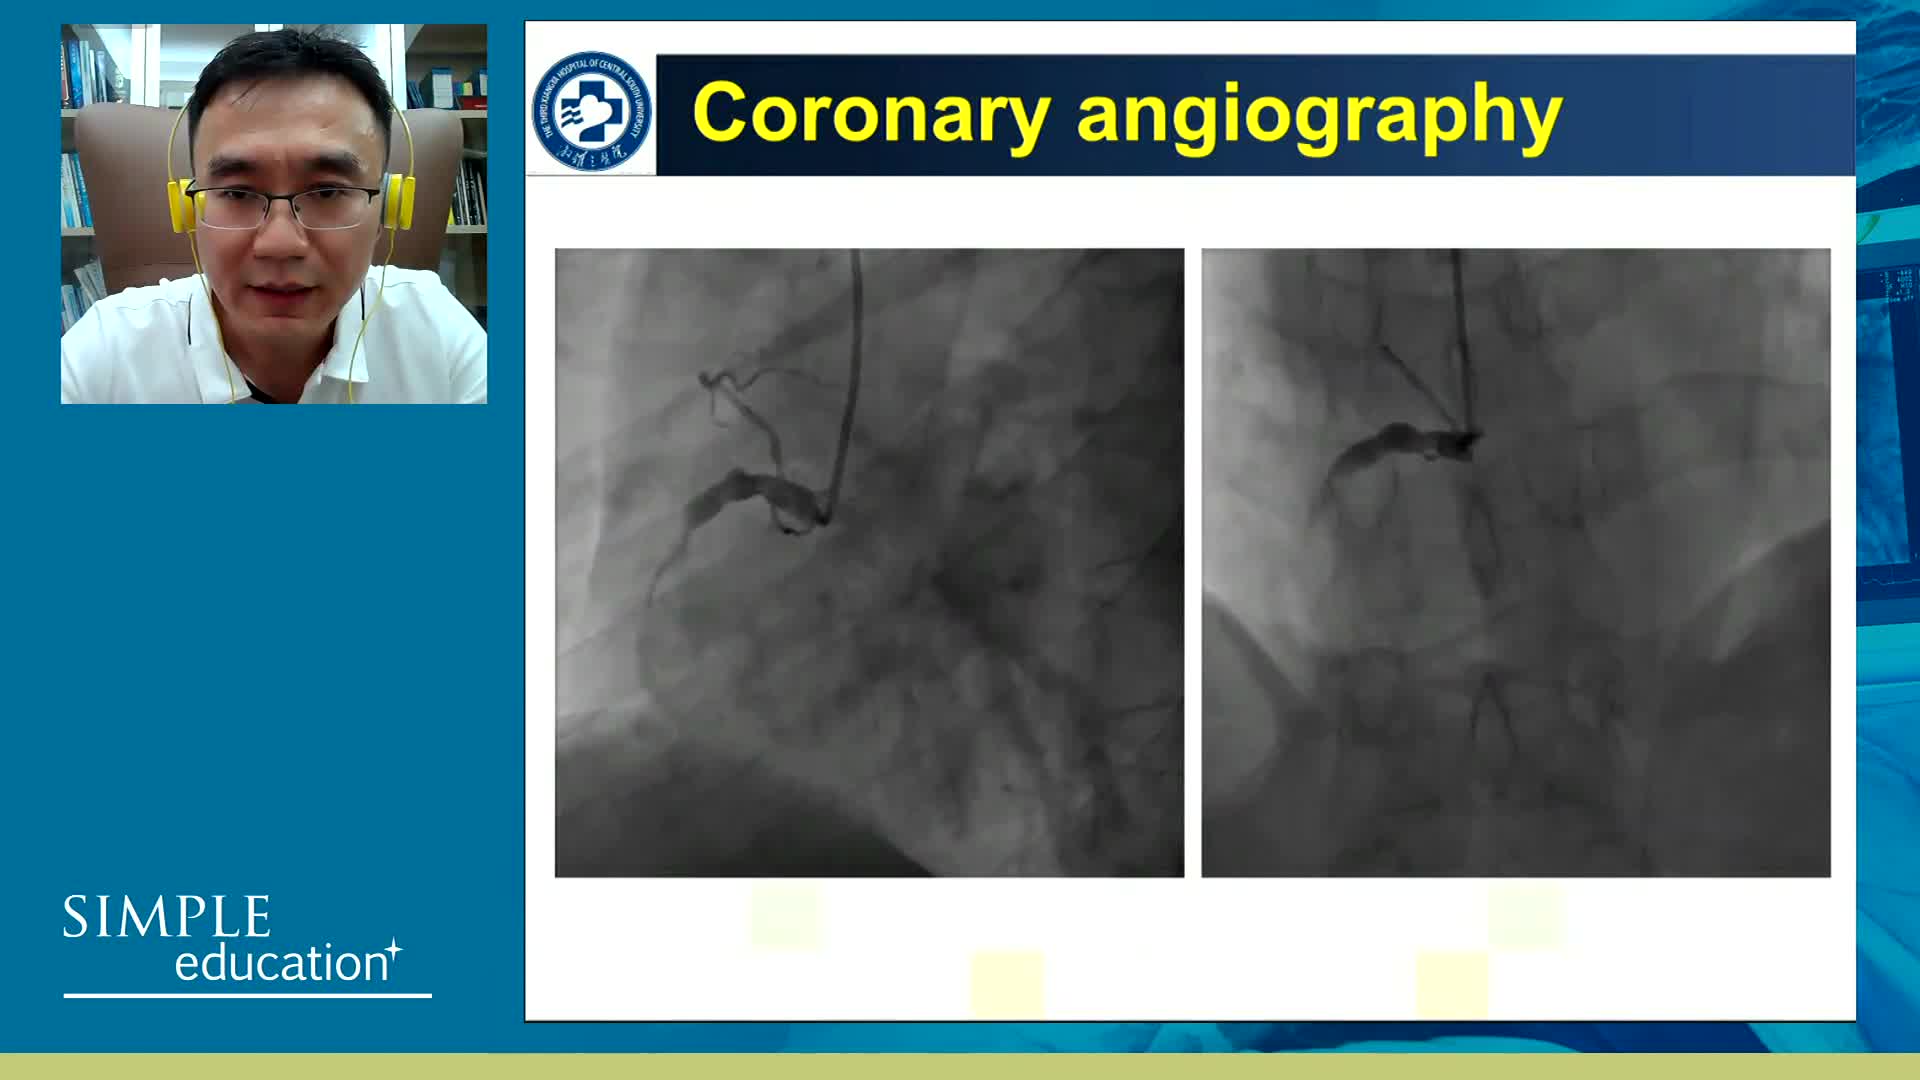

Welcome & Applied coronary physiology to plan and guide PCI-2023 EAPCI Consensus

Coronary physiology gate keeper or guide to coronary PCI? Rationale and design of DEFINE-GPS

Understanding mechanisms of regulation of resting and hyperaemic blood flow, across single and serial stenoses

Best practices and personalised medicine in complex PCI - Prof Javier Escaned

Essential steps for physiology-based PCI planning and guidance - Dr Allen Jeremias

Coronary Bifurcations: An Update on Diagnosis, PCI planning and Imaging and PhysiologyGuidance - Dr Dejan Milasinovic